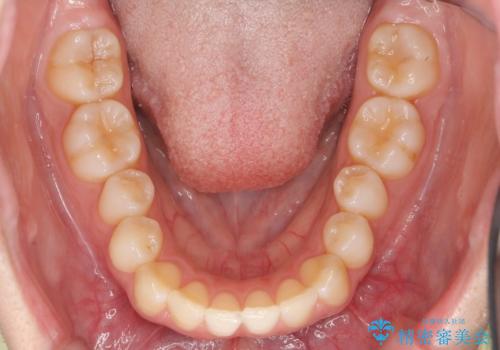

- 出っ歯を主訴に来院。

上の歯を全体に大きく後ろに下げる治療計画を立てました。

後ろに下げるために、親知らずは抜歯しています。